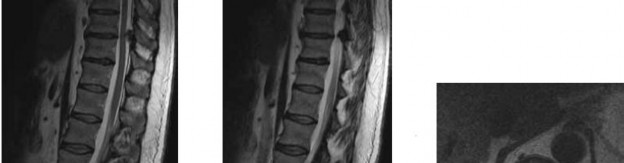

For anyone wondering about ORTHOPEDIC MCQS ONLINE 012 SPINE, When a 56-year-old presents with leg weakness and an unsteady, wide-based gait without discrete lower extremity motor weakness, even with mild lumbar stenosis, the next appropriate action is MRI of the thoracic and cervical spine to evaluate for spinal cord compression. This helps resolve a common diagnostic res question a yearold patient’s symptoms can present, especially when lumbar findings are insufficient.